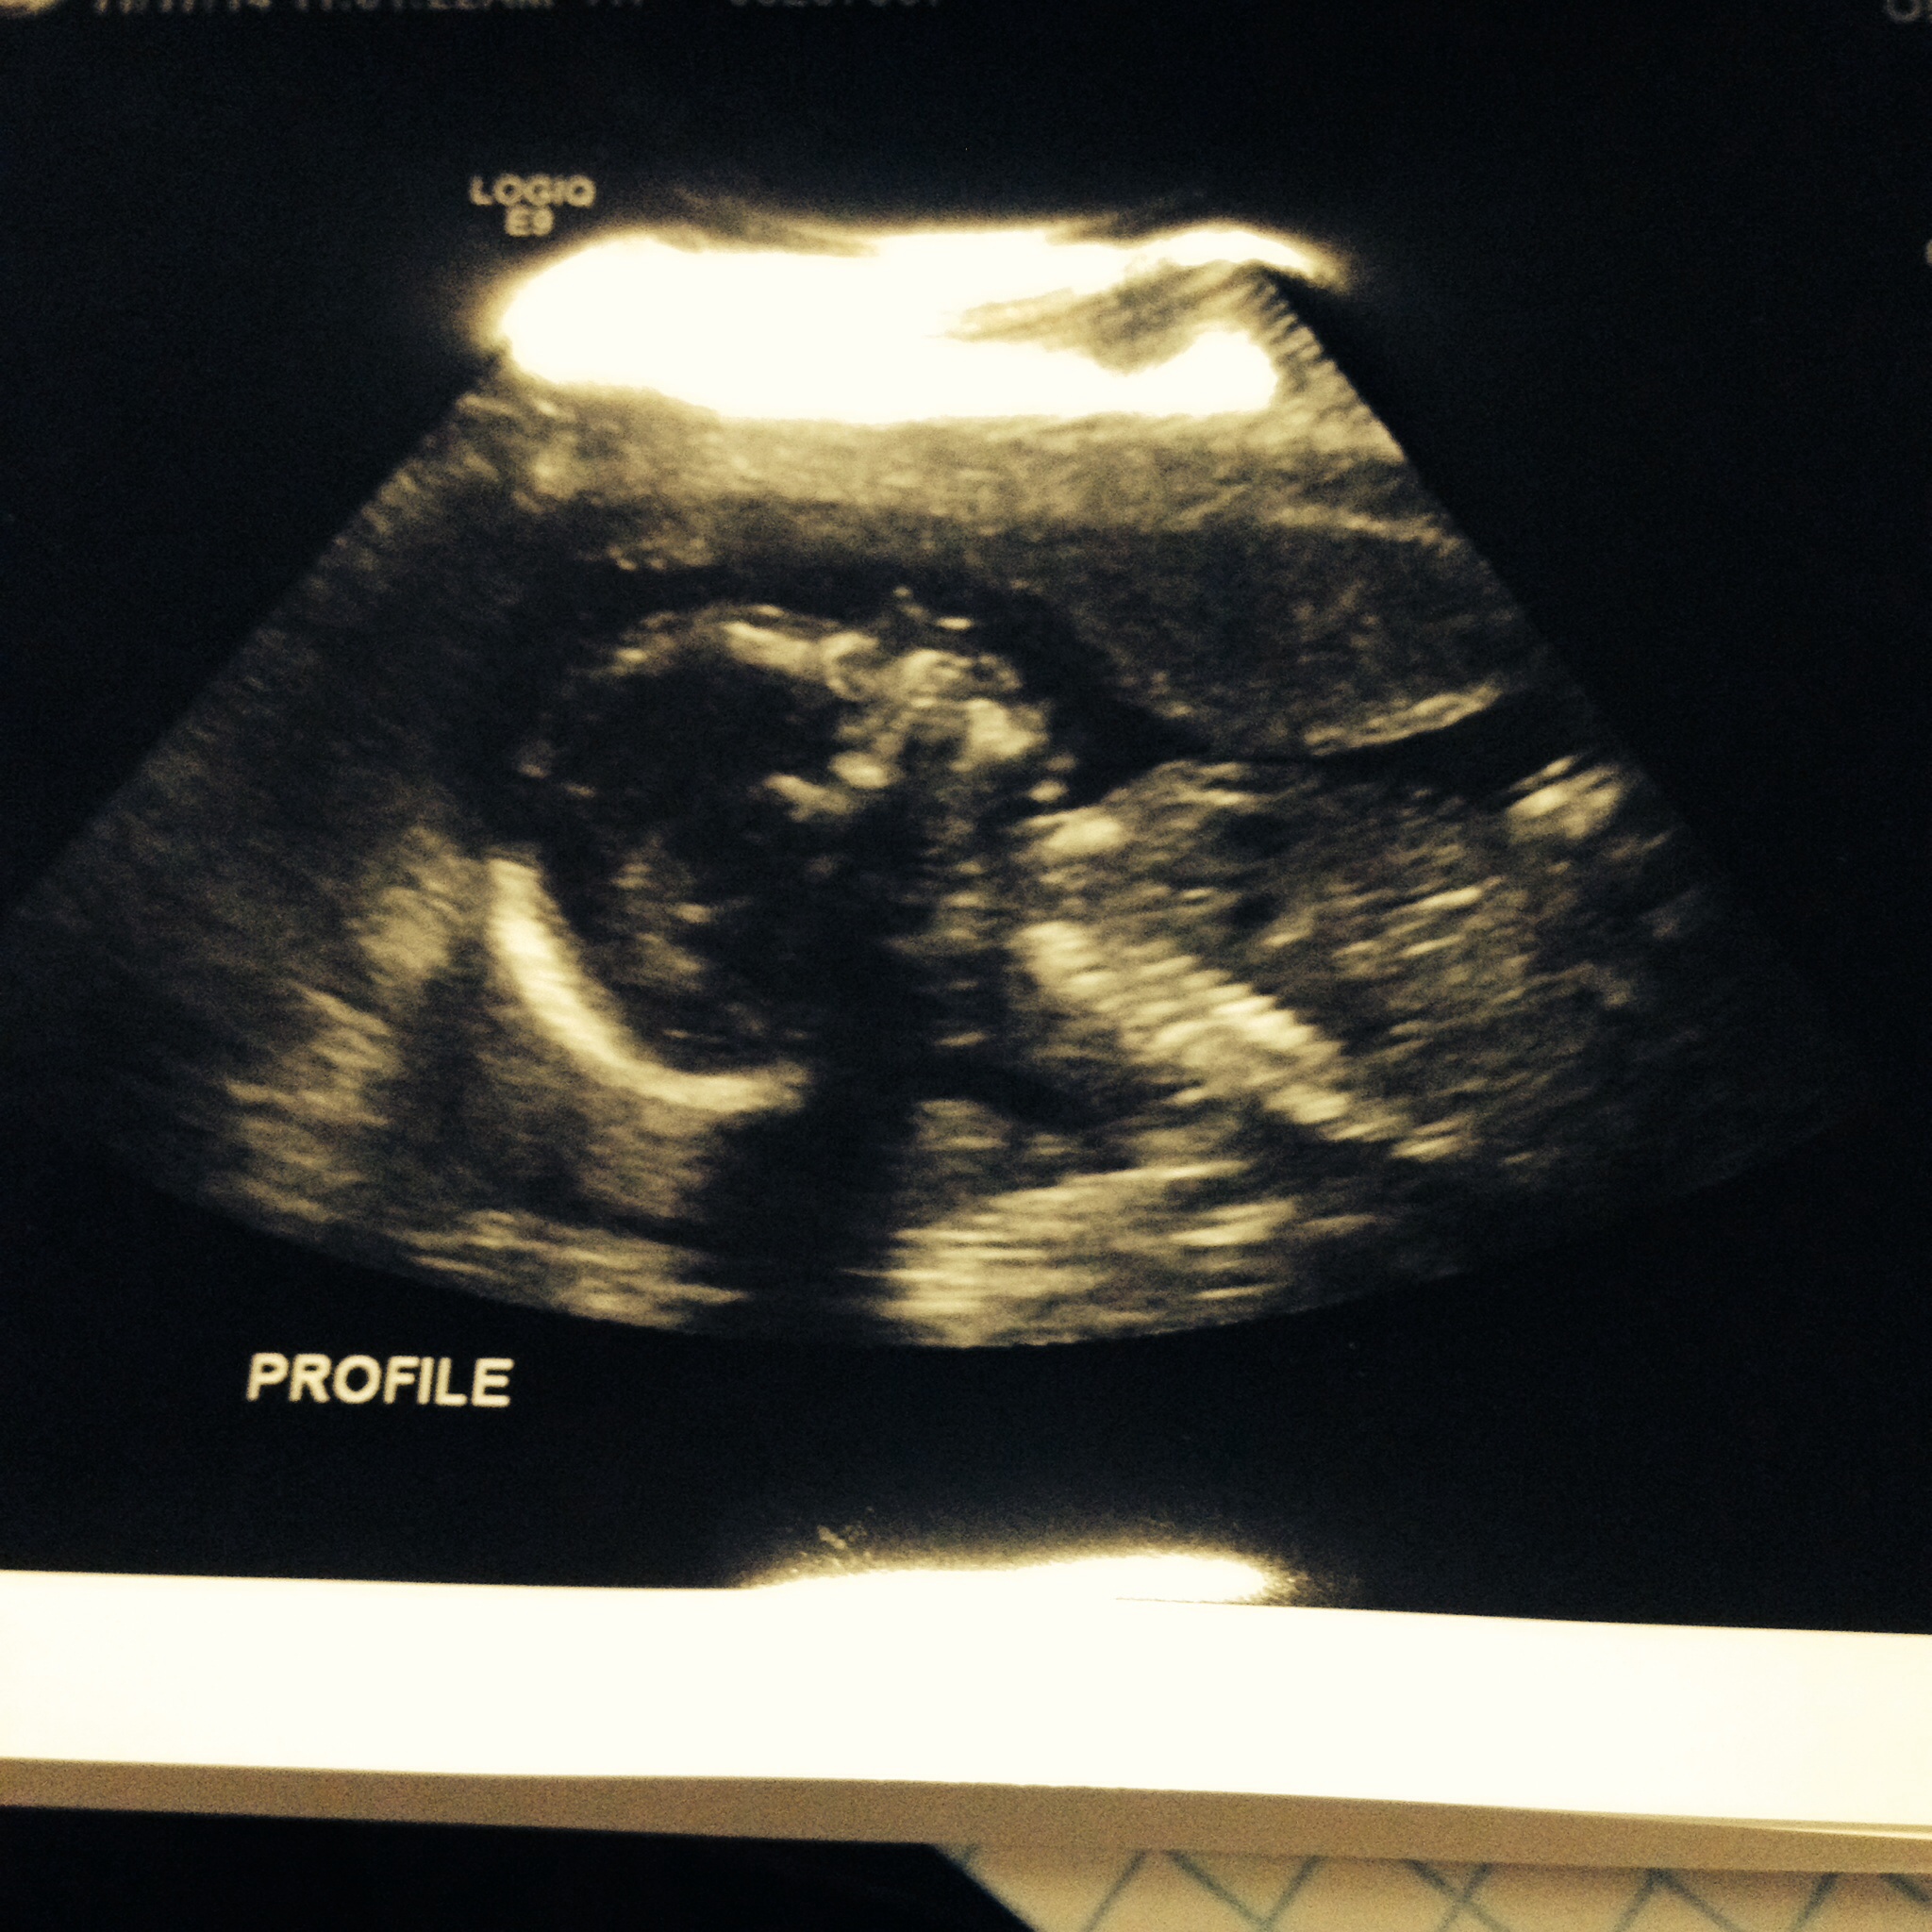

20 weeks tomorrow! Halfway there! Had my a/s yesterday and he curled up in a ball real tight and was not willing to uncurl to get all the pictures the dr needed so I get to go back in 2 weeks for another. But my little man did wave at us! Coolest thing ever.